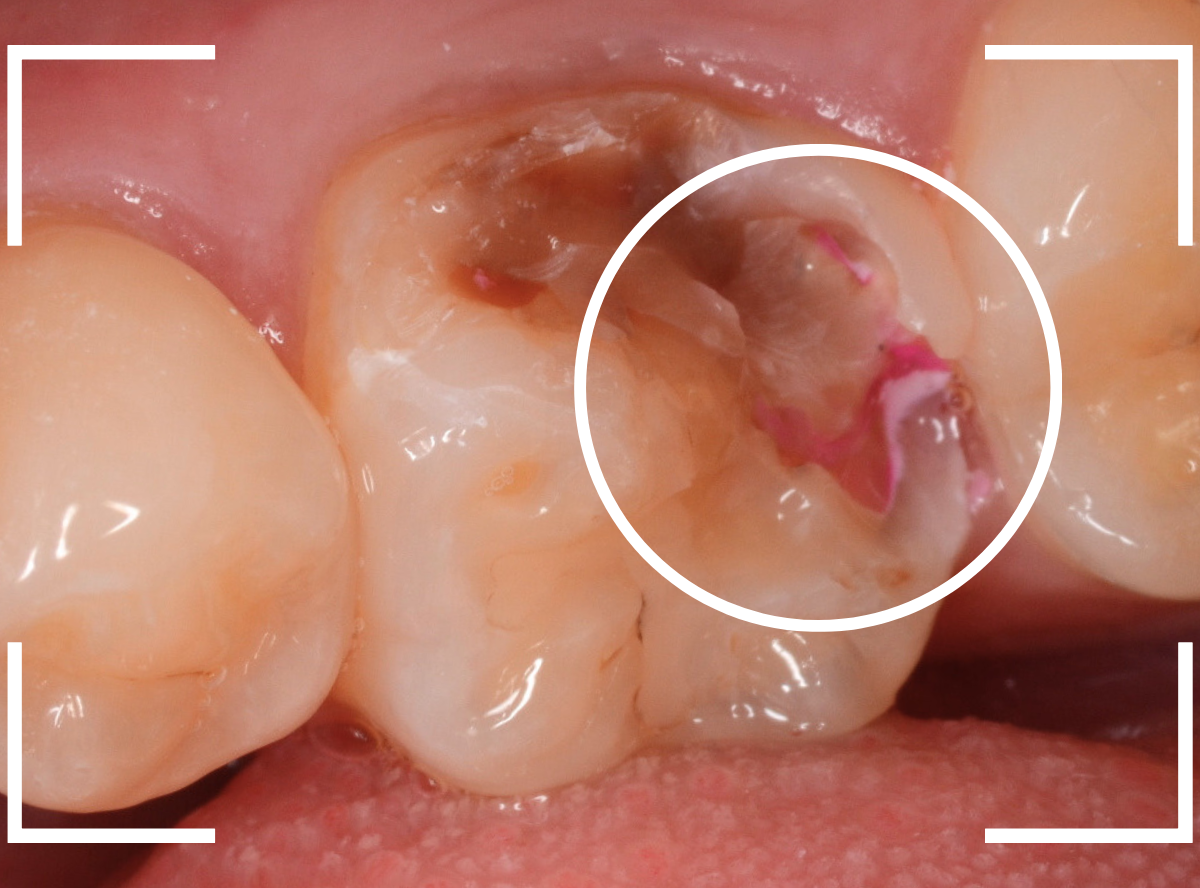

奥歯で咬んだ時に、痛みを感じるという訴えで来院された患者さんです。

パッと見は特に問題なさそうな状態ですが、大きなレジン治療がしてあり、レジンの奥もボヤっと黒っぽく見えてアヤシイ感じです。

麻酔をして、治療を開始します。

レジンを外すと、中から出血してきました。

これは、歯のスキマに歯肉が入り込んでしまったために起こってしまったものです。

おそらく、随分前から虫歯が進行していたと思われます。